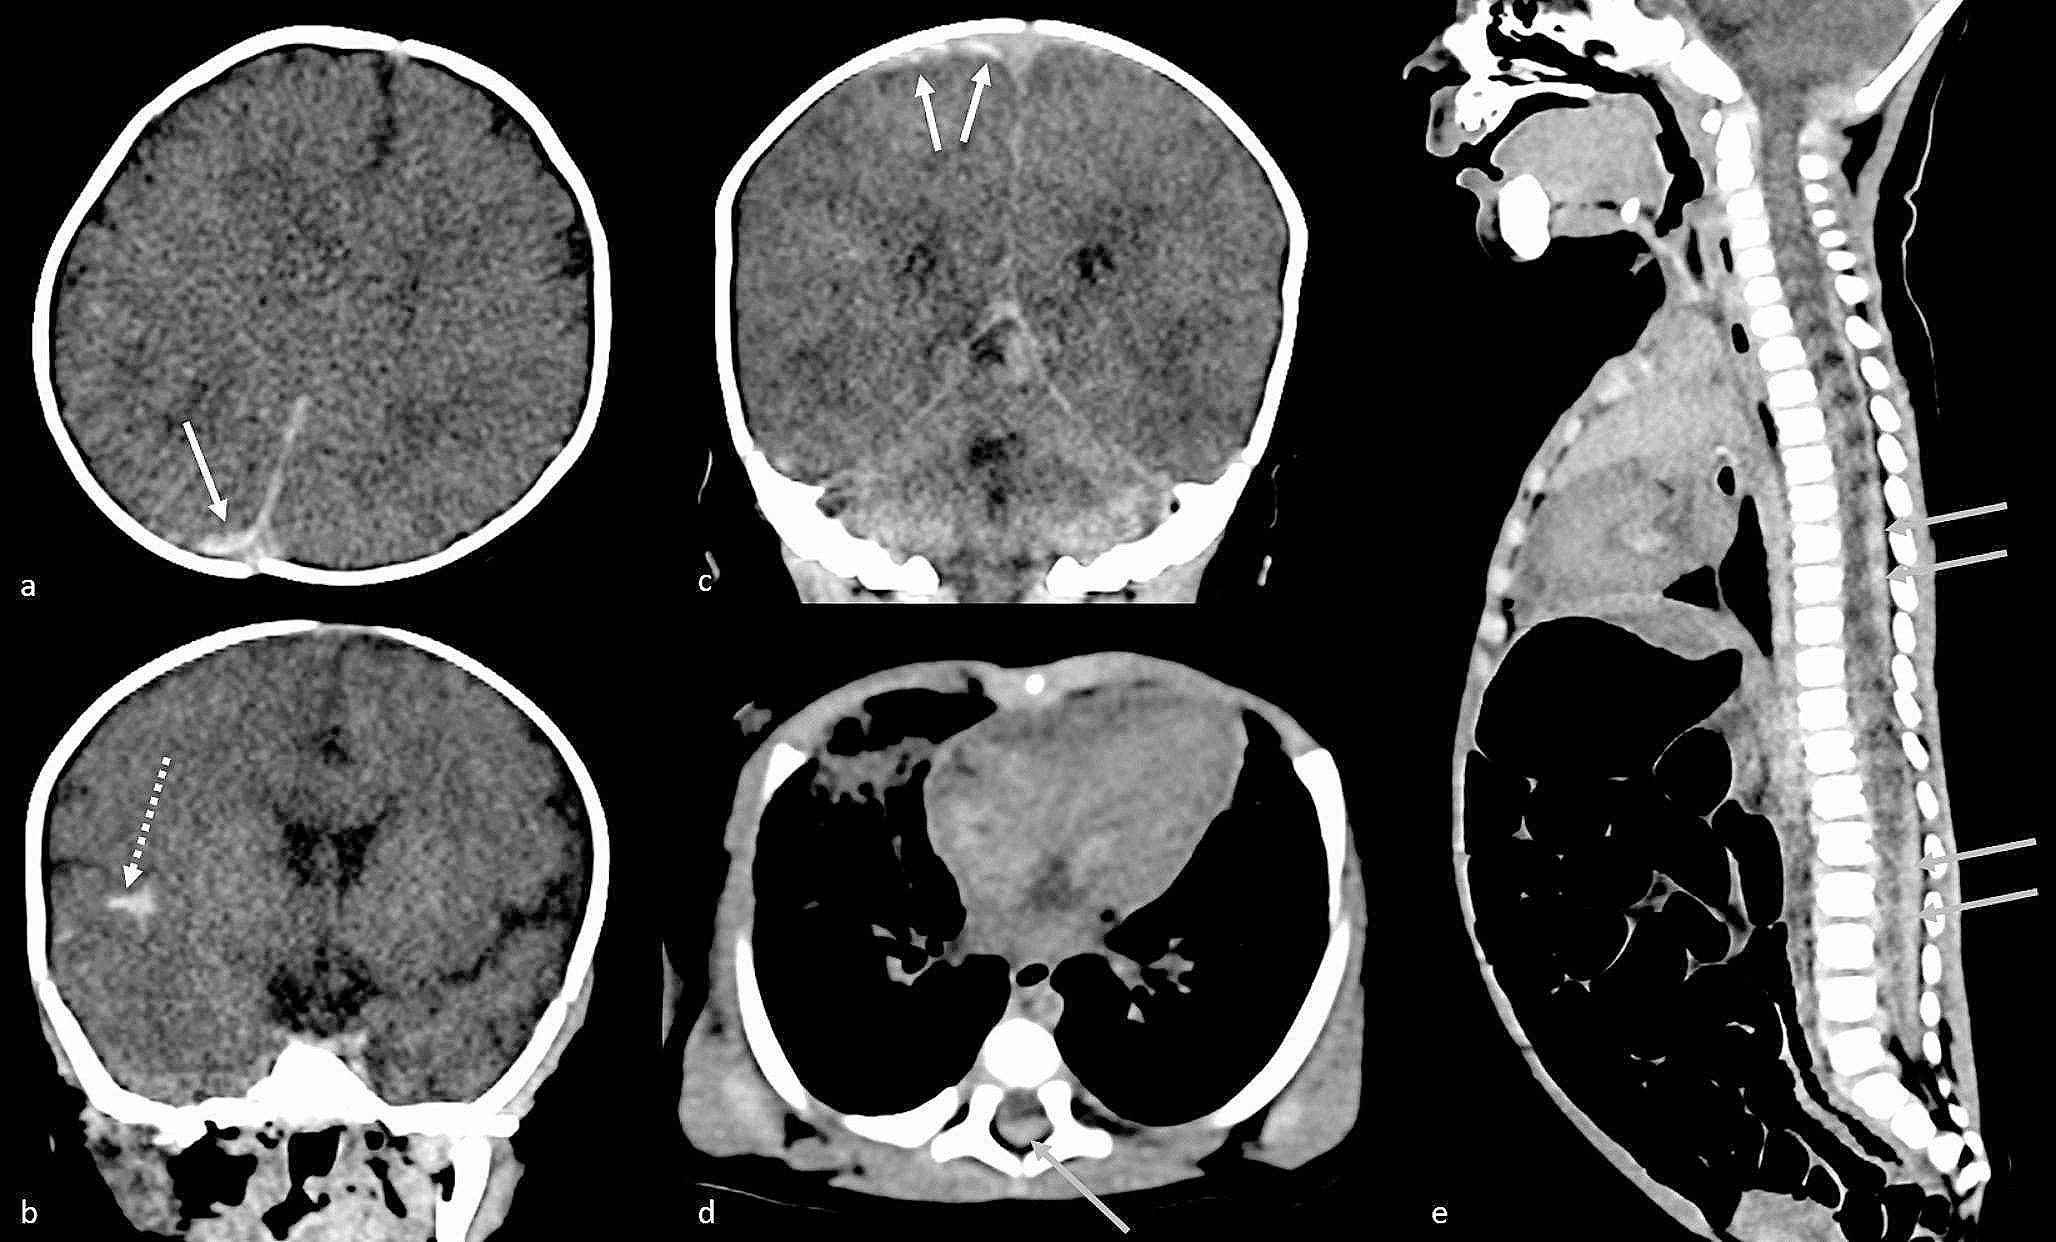

Fig. 2

Post mortem computed tomography. Soft tissue reconstruction. On the axial view of the brain (a), subdural hematoma is visible as a hyperdensity of the subdural space of the parietal convexity (arrow). On the coronal view of the brain (b, c), subarachnoid haemorrhage is visible as a spontaneous hyperdensity of the sylvian fissure (dotted arrow) and temporal subdural hematoma is visible as a lens-like hyperdensity of the subdural space (arrowhead). On the axial (d) and sagittal view (e) of the spinal cord, epidural hematoma is visible as a spontaneous epidural hyperdensity around the spinal cord (gray arrows)

A whole-body post-mortem computed tomography (PMCT) and X ray of the entire skeleton were performed at approximately 6 h after death. PMCT showed a right subdural hematoma, a subarachnoid haemorrhage in the right sylvian fissure and an epidural hematoma (Fig. 1). No fracture was detected on the X ray nor on the PMCT.